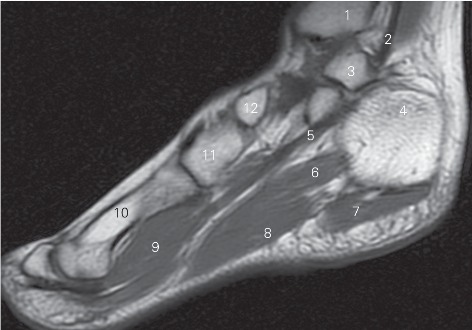

图5-56 经胫骨内髁的矢状断层MR T1加权图像

1 胫骨后肌 tibialis posterior 2 趾长屈肌 flexor digitorum longus

3 内踝 medial malleolus 4

展肌 abductor hallucis

5 舟骨 navicular bone 6 胫骨后肌 tibialis posterior

图5-57 经第一跖骨的矢状断层MR T1加权图像

1 比目鱼肌 soleus 2 踝关节 ankle joint

3 跟腱 achilles tendon 4 足底方肌 quadratus plantae

5 趾短屈肌 flexor digitorum brevis

6 第1跖骨 1st metatarsal bones

7 内侧楔骨 medial cuneiform bone

8 足舟骨 navicular bone 9 距骨 talus

10 胫骨前肌 tibialis anterior 11 胫骨 tibia